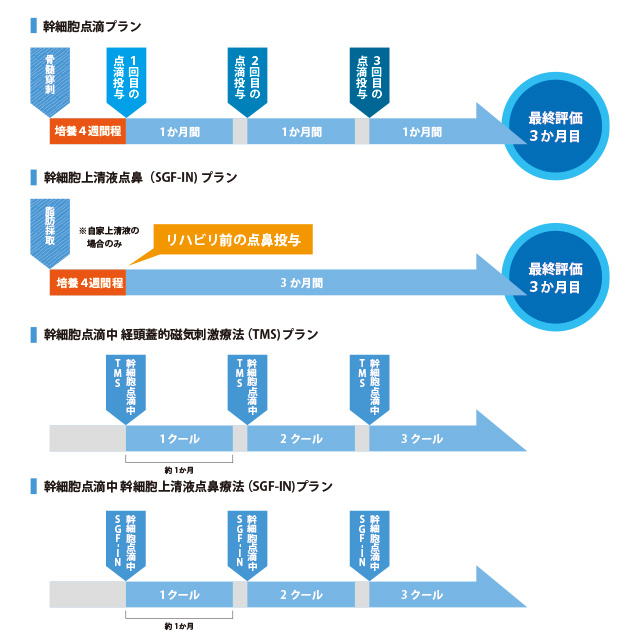

「同時リハビリ×再生医療™」治療プラン

当クリニック独自の「同時リハビリ×再生医療™」の特長の一つは、磁気刺激装置、電気刺激装置、ロボットなどテクノロジーを活用したリハビリを行うことです。

「同時リハビリ×再生医療™」治療プランの流れ